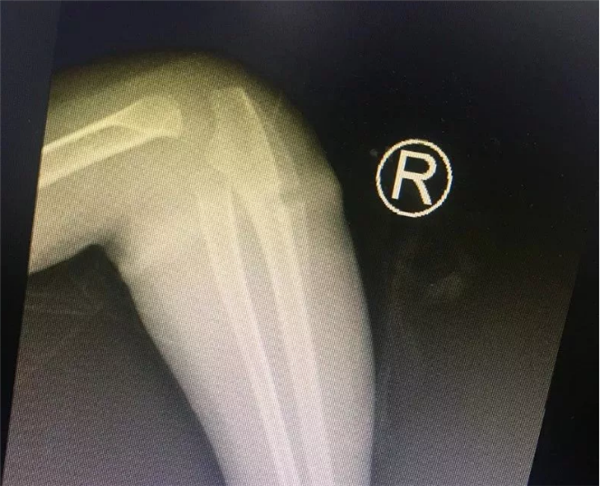

几天前,困扰安徽临泉乐乐一家人半年之久的手臂“圆环”事件终于真相大白了。难以想象的是一根很普通的橡皮筋竟然偷偷“长”进孩子的肉里!最终,浙大儿院湖滨院区骨科叶文松副主任在孩子的手臂中找出橡皮筋,解决了孩子手臂肿胀的痛苦。

叶主任看了乐乐的手臂,告诉孩子的家长,“圆环”很可能是橡皮筋导致的。虽然乐乐父母不大相信,还是听从叶主任的建议,让乐乐入院了。没多久,入院后B超检查结果出来了,也证实了叶主任的诊断是正确的。

有了明确的诊断,骨科各位医生开始为乐乐手术。这个手术并不难,无影灯下,历经半小时就将“圆环”擒拿归案,把长在肉里的环形橡皮筋取了出来,彻底解决了乐乐的病痛。